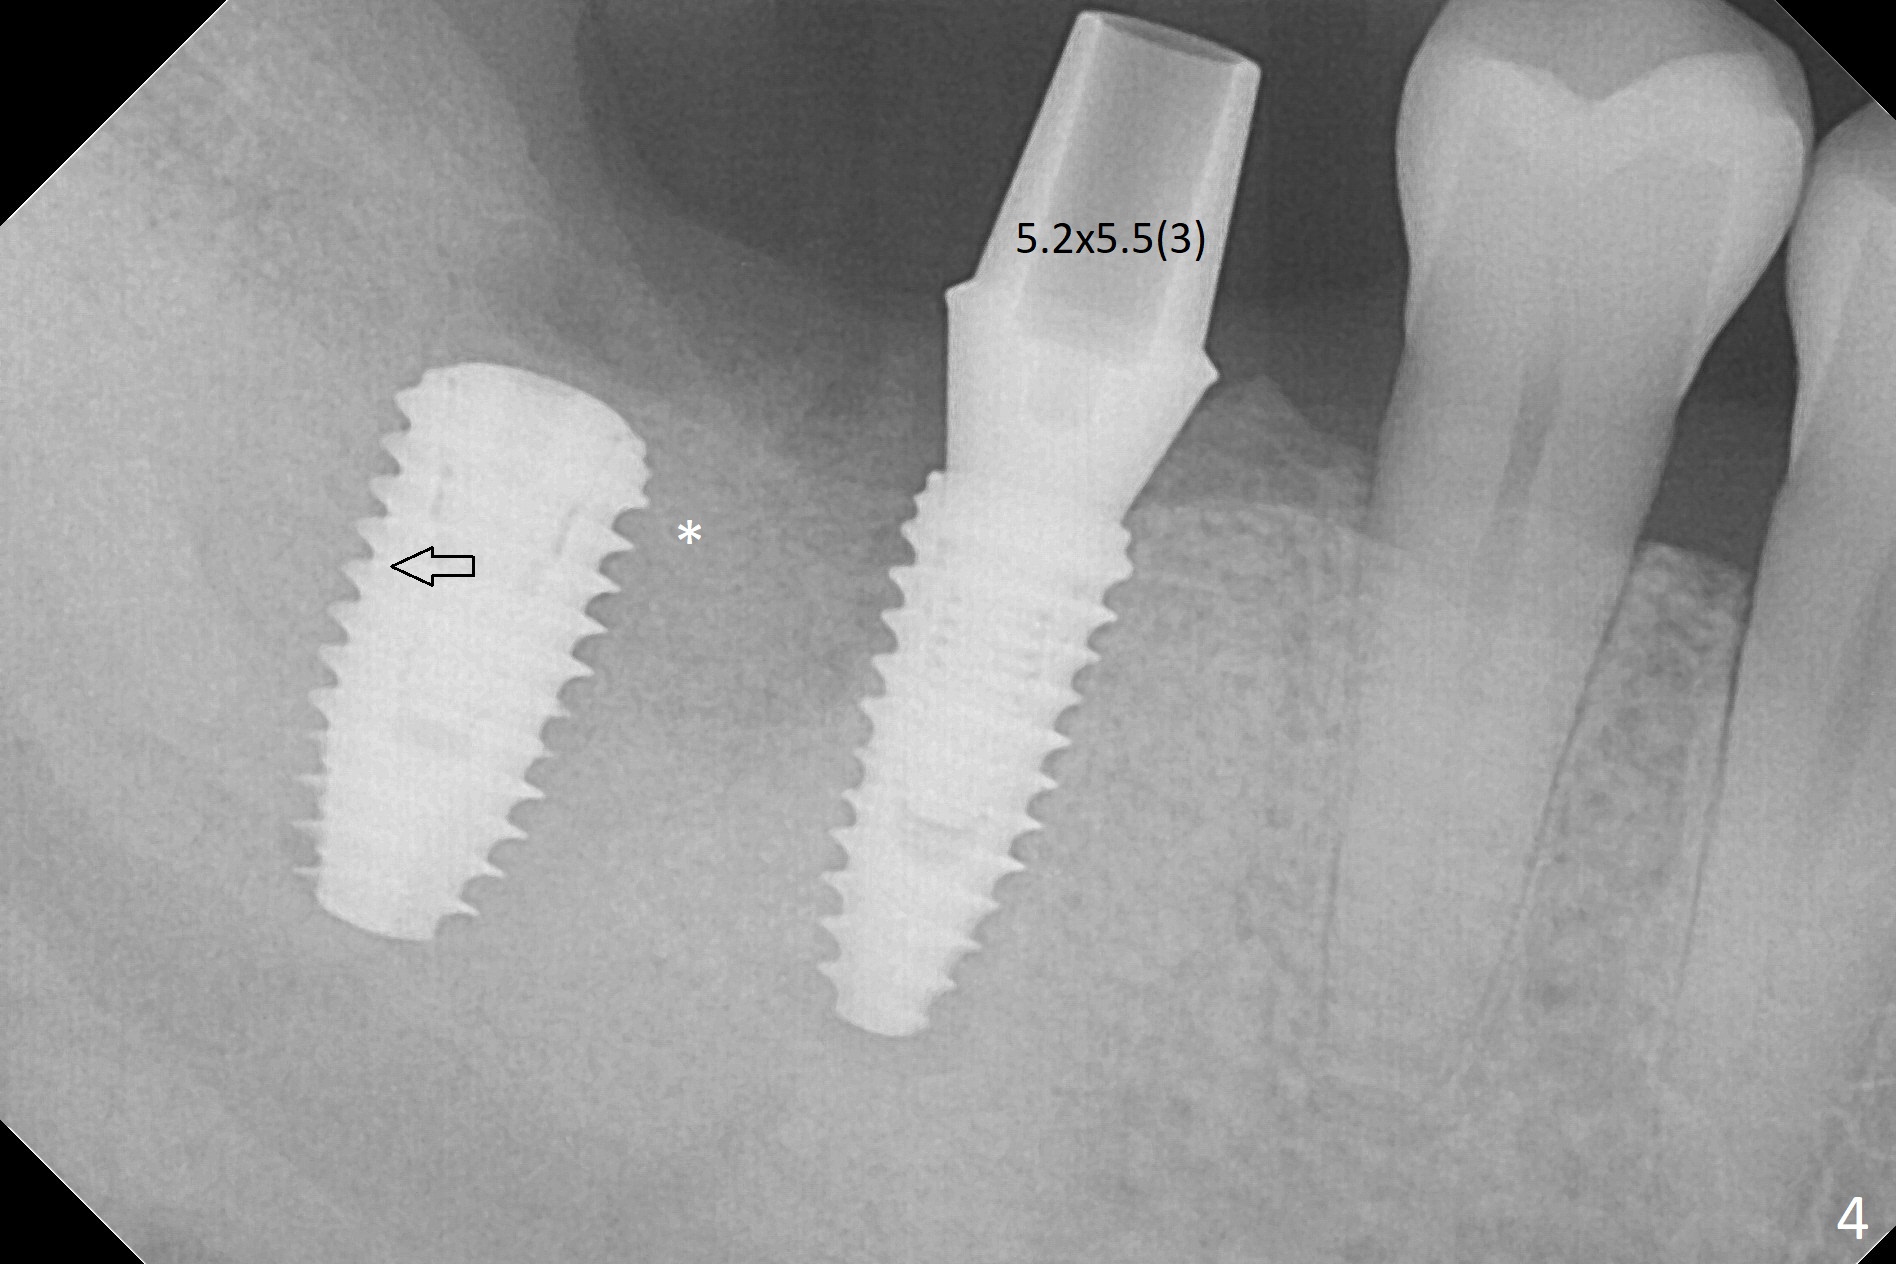

Osteotomy at the sites of #30 and 31 is initiated with Magic Split, followed by Magic Expanders (3.0 and 3.8 mm) at #31.  Initial depth of osteotomy is 13 mm with 2.2 mm drill (Fig.1).  After adjustment of the trajectory at #31 (Fig.1 arrow) and deepening the osteotomy by 2 mm, dummy implants are placed with stability (Fig.2).  Following increase in osteotomy at #31, the larger implant in fact loses stability (Fig.3).  The loose implant is pushed distal (Fig.4 arrow) with placement of autogenous bone mesial (*).  The stable implant at #30 (Fig.3) and its abutment (Fig.4) are used as a post to hold periodontal dressing, which covers the wound at #31 after placement of collagen plug and suturing.  In fact the same technique could be used when socket preservation was performed if an implant were placed at #30 at the same time.  When the periodontal dressing dislodges, the wound at #31 heals uneventfully (Fig.5,6).  The bone graft seems to remain in place 3 months postop (Fig.7).  The implant is uncovered with placement of a 6.8x7 mm healing abutment 4 months postop.  When a cementation abutment is placed and prepped, the buccal margin is much lower than the lingual (Fig.8 taken prior to cementation).  The patient enjoys mastication with the new implant crowns 3.5 months post cementation (Fig.9).